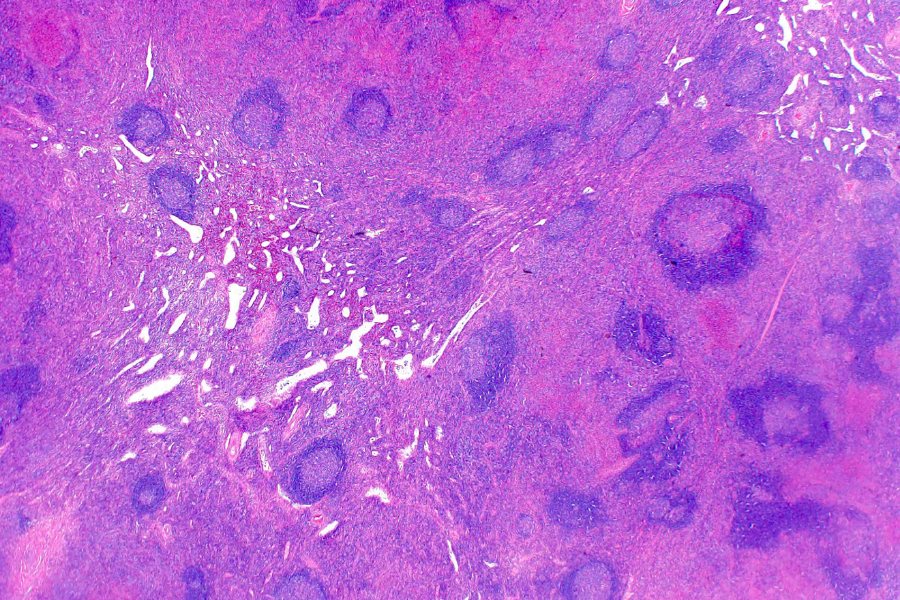

Để chẩn đoán chính xác, bác sĩ có thể chỉ định các phương pháp chẩn đoán hình ảnh như siêu âm, CT hoặc MRI. Trong nhiều trường hợp, cần lấy mẫu mô bằng kim hoặc phẫu thuật để bác sĩ giải phẫu bệnh quan sát dưới kính hiển vi và xác định khối đó là lành tính hay ác tính.